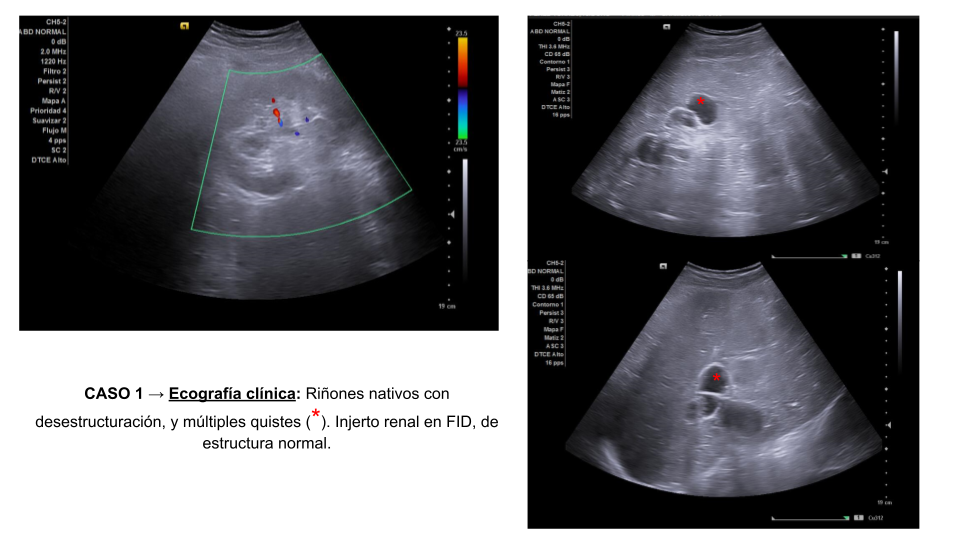

Se presentan dos casos clínicos sometidos a trasplante renal.

Ambos pacientes acuden a su seguimiento habitual.

Descripción de los hallazgos ecográficos y las imágenes más relevantes para la resolución del caso

Estos casos tienen en común: dilatación pielocalicial en los injertos renales postrasplante.